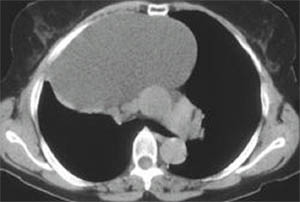

心包囊腫1.X線表現:

①囊腫常發生在心隔角區右側多見。

②囊腫呈圓形或橢圓形密度均勻邊緣清楚。

③側位上囊腫靠前貼近前胸壁。

④透視下胸腔壓力變化可致變形。